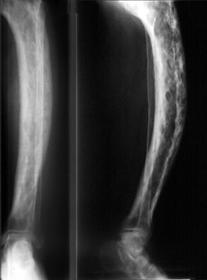

What is seen in this x-ray? 'Sabre' tibia as seen in Paget's DS.